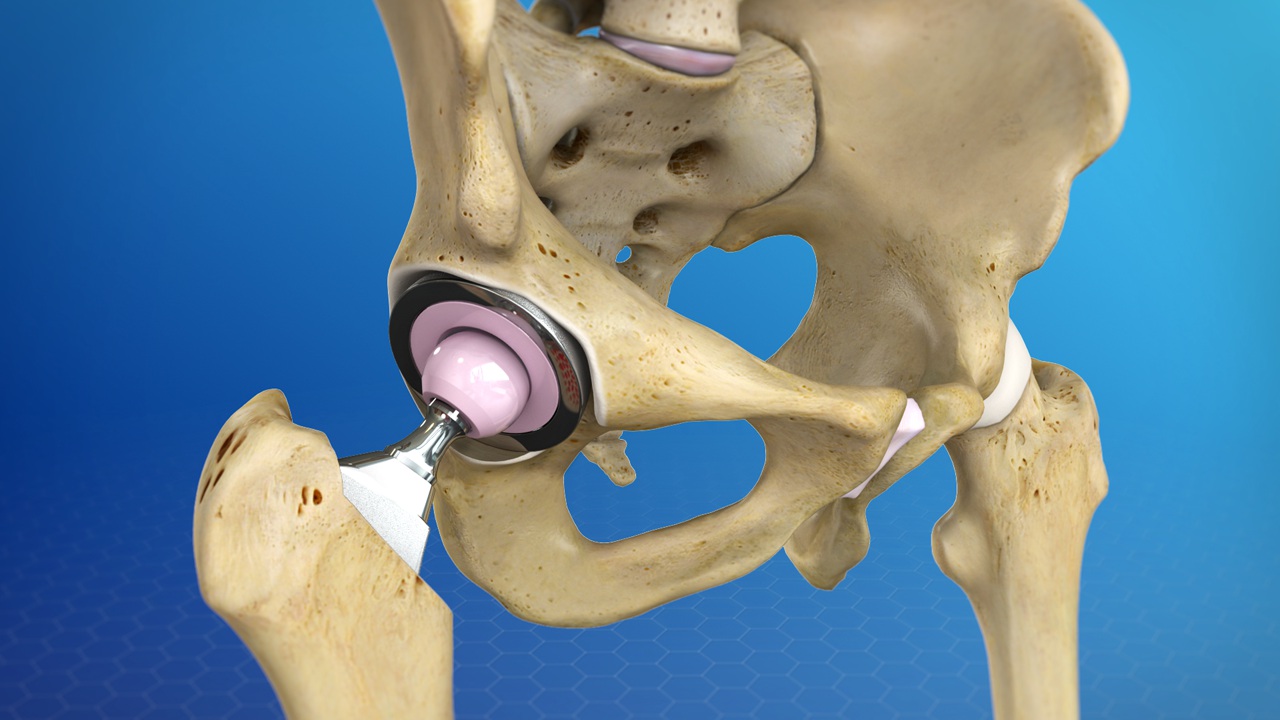

Hip replacement, or hip arthroplasty, is a surgical procedure where a damaged or arthritic hip joint is replaced with a prosthetic implant. This procedure is recommended for individuals suffering from chronic hip pain due to arthritis, sports injuries, or degenerative conditions. Dr. Lokesh Yogi and his team at Jaipur Ortho are leaders in minimally invasive hip replacement surgery, offering precise treatment plans for faster recovery and long-term success.

- Total Hip Replacement (THR): Replacement of both the ball and socket of the hip joint.